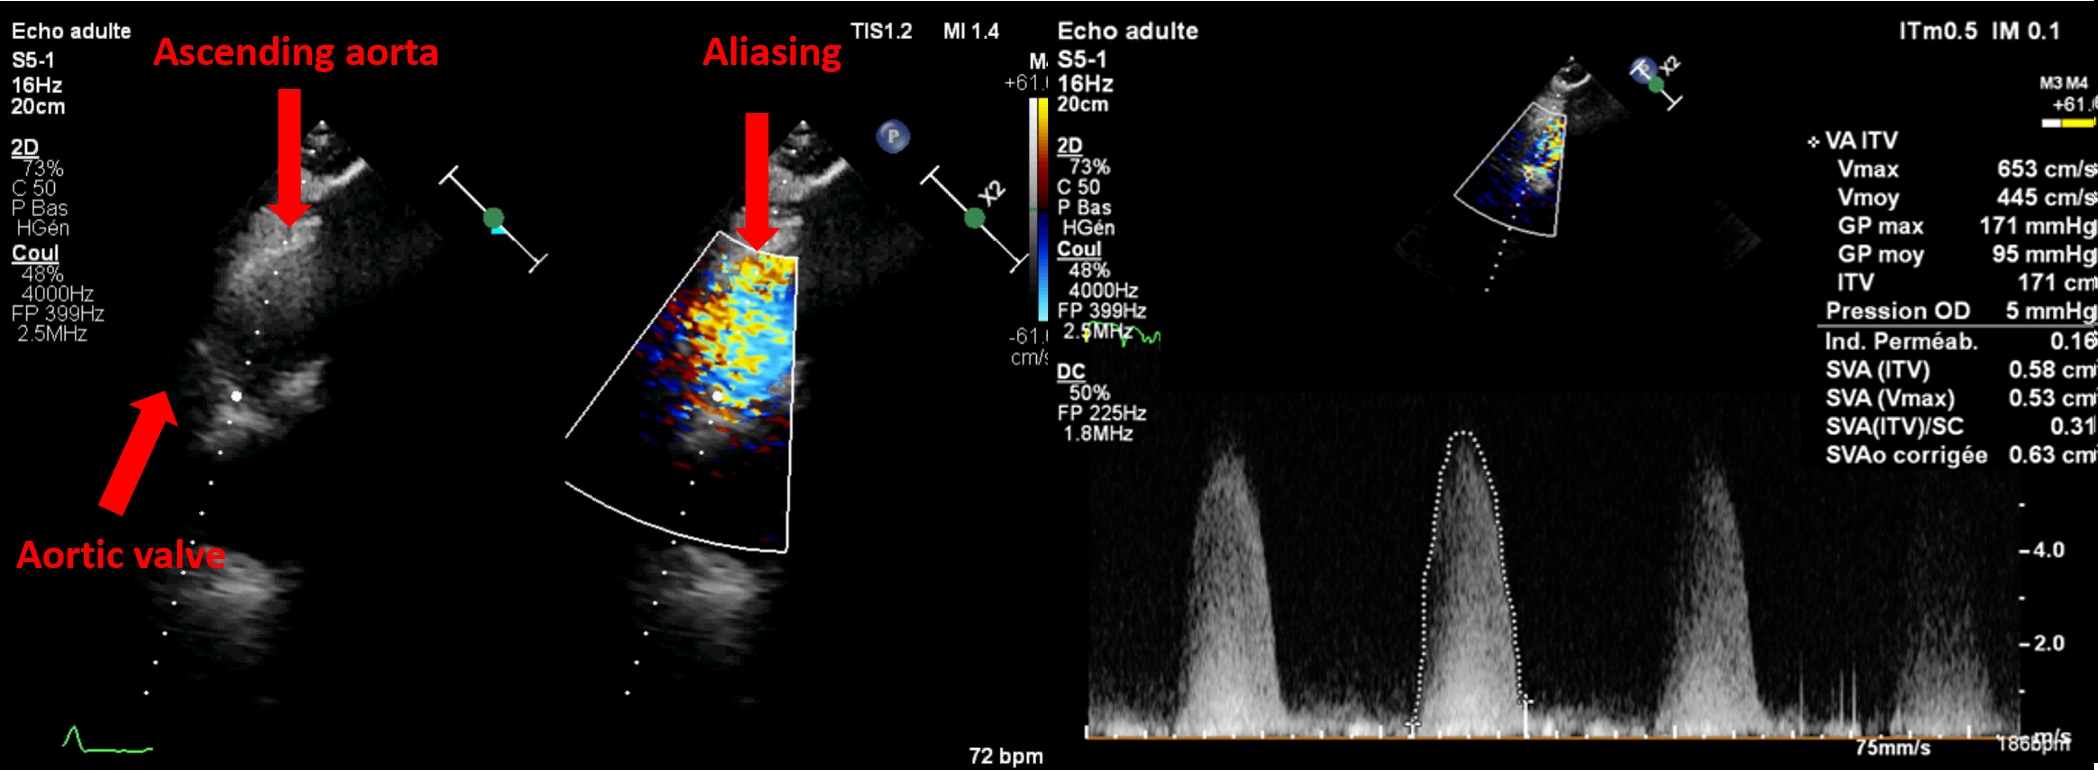

Severe AS has a worse prognosis than mild or moderate AS, and the degree of severity helps stratify risk even among severe cases [3–5]. About ten years ago, the Vienna group reported reduced event-free survival (death or AVR) as maximum velocity (Vmax) increased and introduced the concept of “very severe” or “critical” AS [3]. Based on this, U.S. guidelines in 2014 adopted a threshold of 5 m/s for early surgery in low-risk patients, whereas European guidelines used 5.5 m/s in 2012 and 2017 due to a lack of mortality data. Collaborative work with our team and Saint Philibert Hospital (Lomme) identified increased mortality starting at a Vmax of 5 m/s [4] or a mean gradient >60 mmHg [5] in over 1,100 asymptomatic or mildly symptomatic patients with high-gradient (≥40 mmHg), severe AS with preserved LVEF. These and other multicentre studies [6] helped shape updated European guidelines which now recommend AVR (surgical or percutaneous, depending on age and access) for asymptomatic severe AS with Vmax >5 m/s and/or mean gradient ≥60 mmHg, if procedural risk is low [2]. Doppler  measurements must be meticulously performed to avoid missing "very severe" AS. Also, apical-only views are insufficient. A multi-window approach (right parasternal++, suprasternal, supraclavicular, subcostal) using Pedoff or even standard 2D probes with colour Doppler (Figure 2) often detects higher gradients than apical views alone in at least one quarter of cases.

Figure 2. Interest of a multi view approach in asymptomatic aortic stenosis.

The use of a standard 2D probe allows visualisation of aliasing in the ascending aorta to obtain optimal alignment. In this patient, a Vmax of 4.3 m/s was recorded from the apical 5-chamber view, increasing to over 6 m/s from the right parasternal view — thus reclassifying the aortic stenosis from severe to very severe.